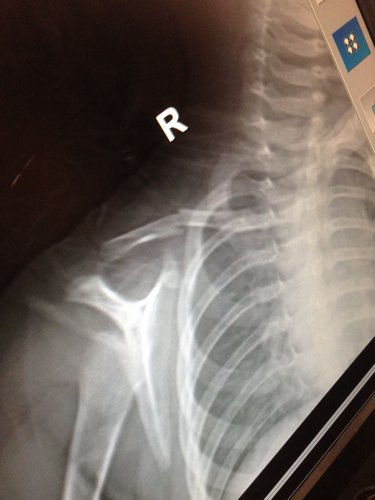

我家孩子从自行车摔倒,拍片子发现锁骨骨折,孩子现在1岁6个月,请问大夫应该如何治疗,需要手术吗?

您好,这个需要手术治疗,要用钢板固定。医生做完钢板固定手术大约3个月到半年后,会进行第二次手术,通过第二次手术把钢板取出。然后您的宝宝还要经过半年到一年的康复时间,最后,您的宝宝就可以痊愈的。提醒一下:钢板取出后,最好不要让宝宝的右手受到伤害,同时,您们也要是不是的抬抬宝宝的手,让宝宝握拳头,一定要...慢慢的,要有信心,可能刚开始的一两个月宝宝会说疼,您可以叫宝宝慢慢的;还有,刚开始的一两个月您们要握着宝宝的手,您们先教宝宝。原因是:宝宝可能不会用劲,也有可能用劲过大,又会伤害到骨头。祝愿宝宝早点康复,谢谢,望采纳。

楼主。我不是医生但是从片子上看骨头断了。肯定要做手术的,不然会有后遗症得,希望采纳